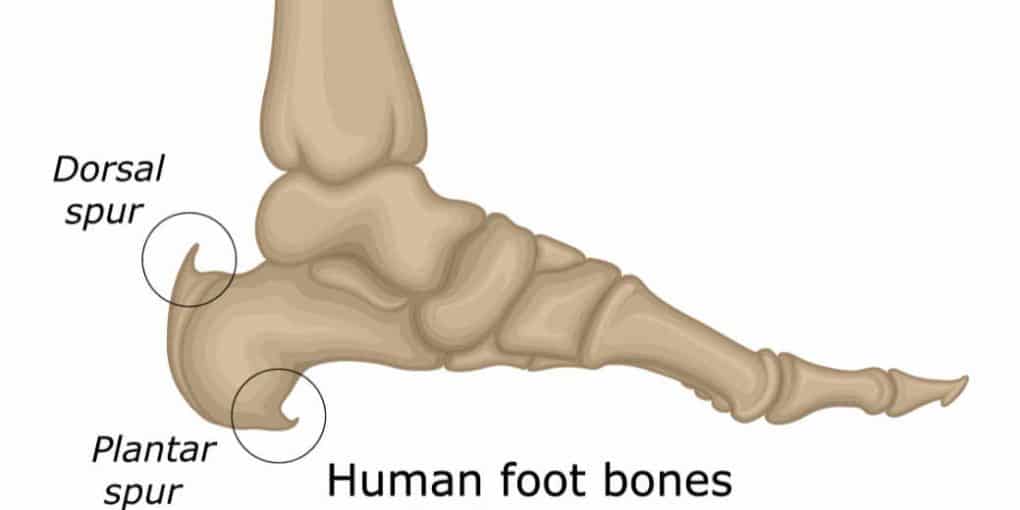

Heel Spur

A heel spur is a calcium deposit causing a bony protrusion in two possible places. The first is on the underside of the heel bone, and the second can be at the insertion of the Achilles tendon to the heel bone.

Although heel spurs are often painless, they can cause heel pain. They are frequently associated with plantar fasciitis or achilles tendonitis.

This process usually occurs over a period of many months. Heel spurs are often caused by strains on foot muscles and ligaments, stretching of the tendons, and repeated tearing of the membrane that covers the heel bone. Heel spurs are especially common among athletes whose activities include large amounts of running and jumping.